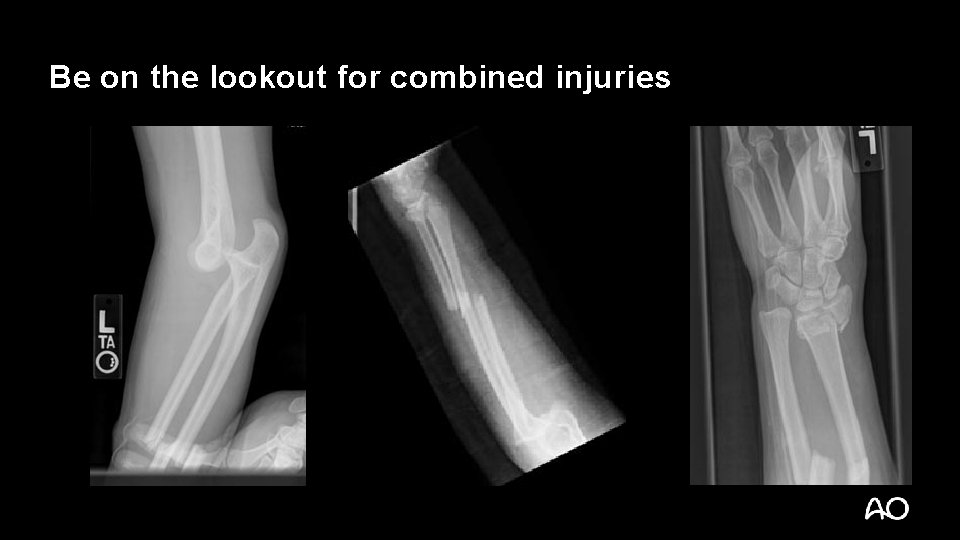

Be on the lookout for combined injuries